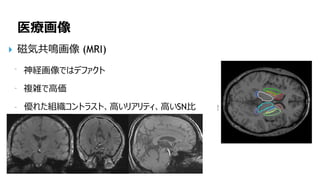

医療画像

磁気共鳴画像 (MRI)

神経画像ではデファクト

複雑で高価

優れた組織コントラスト、高いリアリティ、高いSN比